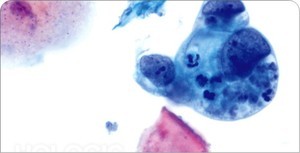

A 60 year-old woman presents with post-menopausal bleeding. You perform an endometrial biopsy and find the following cell types:

Endometrial carcinoma:

Most common gynecological malignancy

- Peak at 55-65 years

- Presentation= vaginal bleeding (typically preceded by endometrial hyperplasia)

Endometrial adenocarcinoma: 70% present at stage 1, surgery is sufficient for treatment. 5-year 96% survival with no metastases vs 66% with metastatic spread

Endometrial lining connects to vagina- presents early. ANY post-menopausal bleeding needs to be worked up (~10% associated with endometrial cancer)